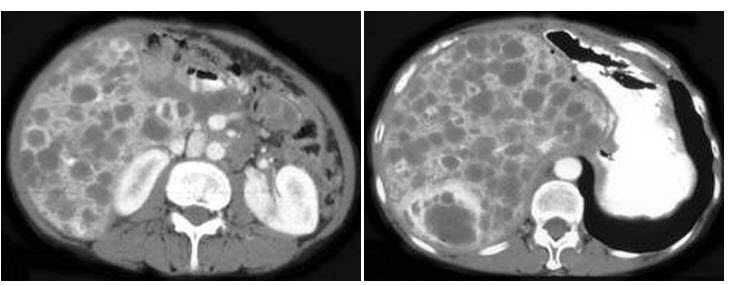

19、多项选择题

女,44岁,突发性胁腹部绞痛并向会阴部放射伴血尿一次,CT扫描如图所示,下列说法正确的是()

A.右侧肾盂肾盏扩张

B.右输尿管中上段扩张

C.右输尿管内可见沿输尿管走行的高密度影

D.右输尿管结石

E.左肾输尿管未见异常

点击查看答案

本题答案:微信扫下方二维码即可打包下载完整带答案解析版《★放射医学(医学高级)》或《放射医学(医学高级):CT》题库